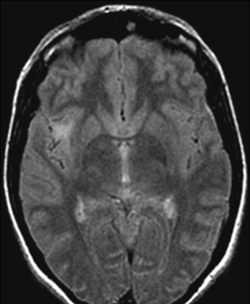

43歲的陳女士是一名建筑師,在檢查出腦瘤之前沒有沒有明顯的既往病史,身體一向也很健康。據(jù)她回憶,2008年5月因頭痛接受了腦部MRI檢查,MRI顯示左側(cè)小的頸內(nèi)動脈眼段動脈瘤(未治療)以及右側(cè)島葉病變,高度提示低級別膠質(zhì)瘤(t1加權(quán)MRI無增強低信號病變,F(xiàn)LAIR MRI呈高信號)(圖1)。島葉是大腦旁邊緣系統(tǒng)的一個重要結(jié)構(gòu)。島葉皮質(zhì)是舊皮質(zhì)和新皮質(zhì)相連的中間皮質(zhì)結(jié)構(gòu),島葉與整個大腦皮質(zhì)及皮質(zhì)下核團均有豐富的神經(jīng)聯(lián)系,是個多種功能的匯集區(qū)域。島葉的功能主要包括內(nèi)臟感覺、輔助運動、軀體感覺、聽覺功能以及復(fù)雜的語言功能,同時協(xié)調(diào)來自于自身情感意識的內(nèi)部和外部信息,在經(jīng)驗、情感和行為活動中起平衡作用。陳女士目前神經(jīng)檢查是正常的,也可以正常生活。如果沒有這次檢查,陳女士甚至認(rèn)為是不是可以一直忽略腫瘤的存在。

圖1:2008年5月軸向FLAIR磁共振圖像顯示,右側(cè)島葉低級別膠質(zhì)瘤,腫瘤體積為3cm³

低級別膠質(zhì)瘤通常處于非活動狀態(tài),但是不少腫瘤較終會演變成致命性的高級別膠質(zhì)瘤。陳女士在隨訪中發(fā)現(xiàn)腫瘤正在緩慢持續(xù)增長,較終于2014年2月轉(zhuǎn)正至對其手術(shù)有把握的神經(jīng)外科中心進行咨詢。當(dāng)時,醫(yī)院使用專用軟件(Myrian,Intrasense)回顧性計算了一開始和較后一次MRI檢查的腫瘤體積。在一開始影像學(xué)研究(2008年5月)中,腫瘤體積為3cm³(圖1),而在較后一次影像學(xué)研究(2013年11月)中,病變體積為11cm³(圖2)。平均腫瘤直徑生長速度為每年1.8 mm,這符合低級別膠質(zhì)瘤的自然進程(Therefore,the mean spontaneous velocity of diametric expansion before firstline treatment,i.e.,the slope of the mean tumor diameter growth curve deduced using the methodology detailed by Pallud et al.,was 1.8 mm/year.)。在與患者及其家人的訪談結(jié)束時,由于多年來腫瘤體積的客觀增加,決定并計劃于2014年4月進行手術(shù)。